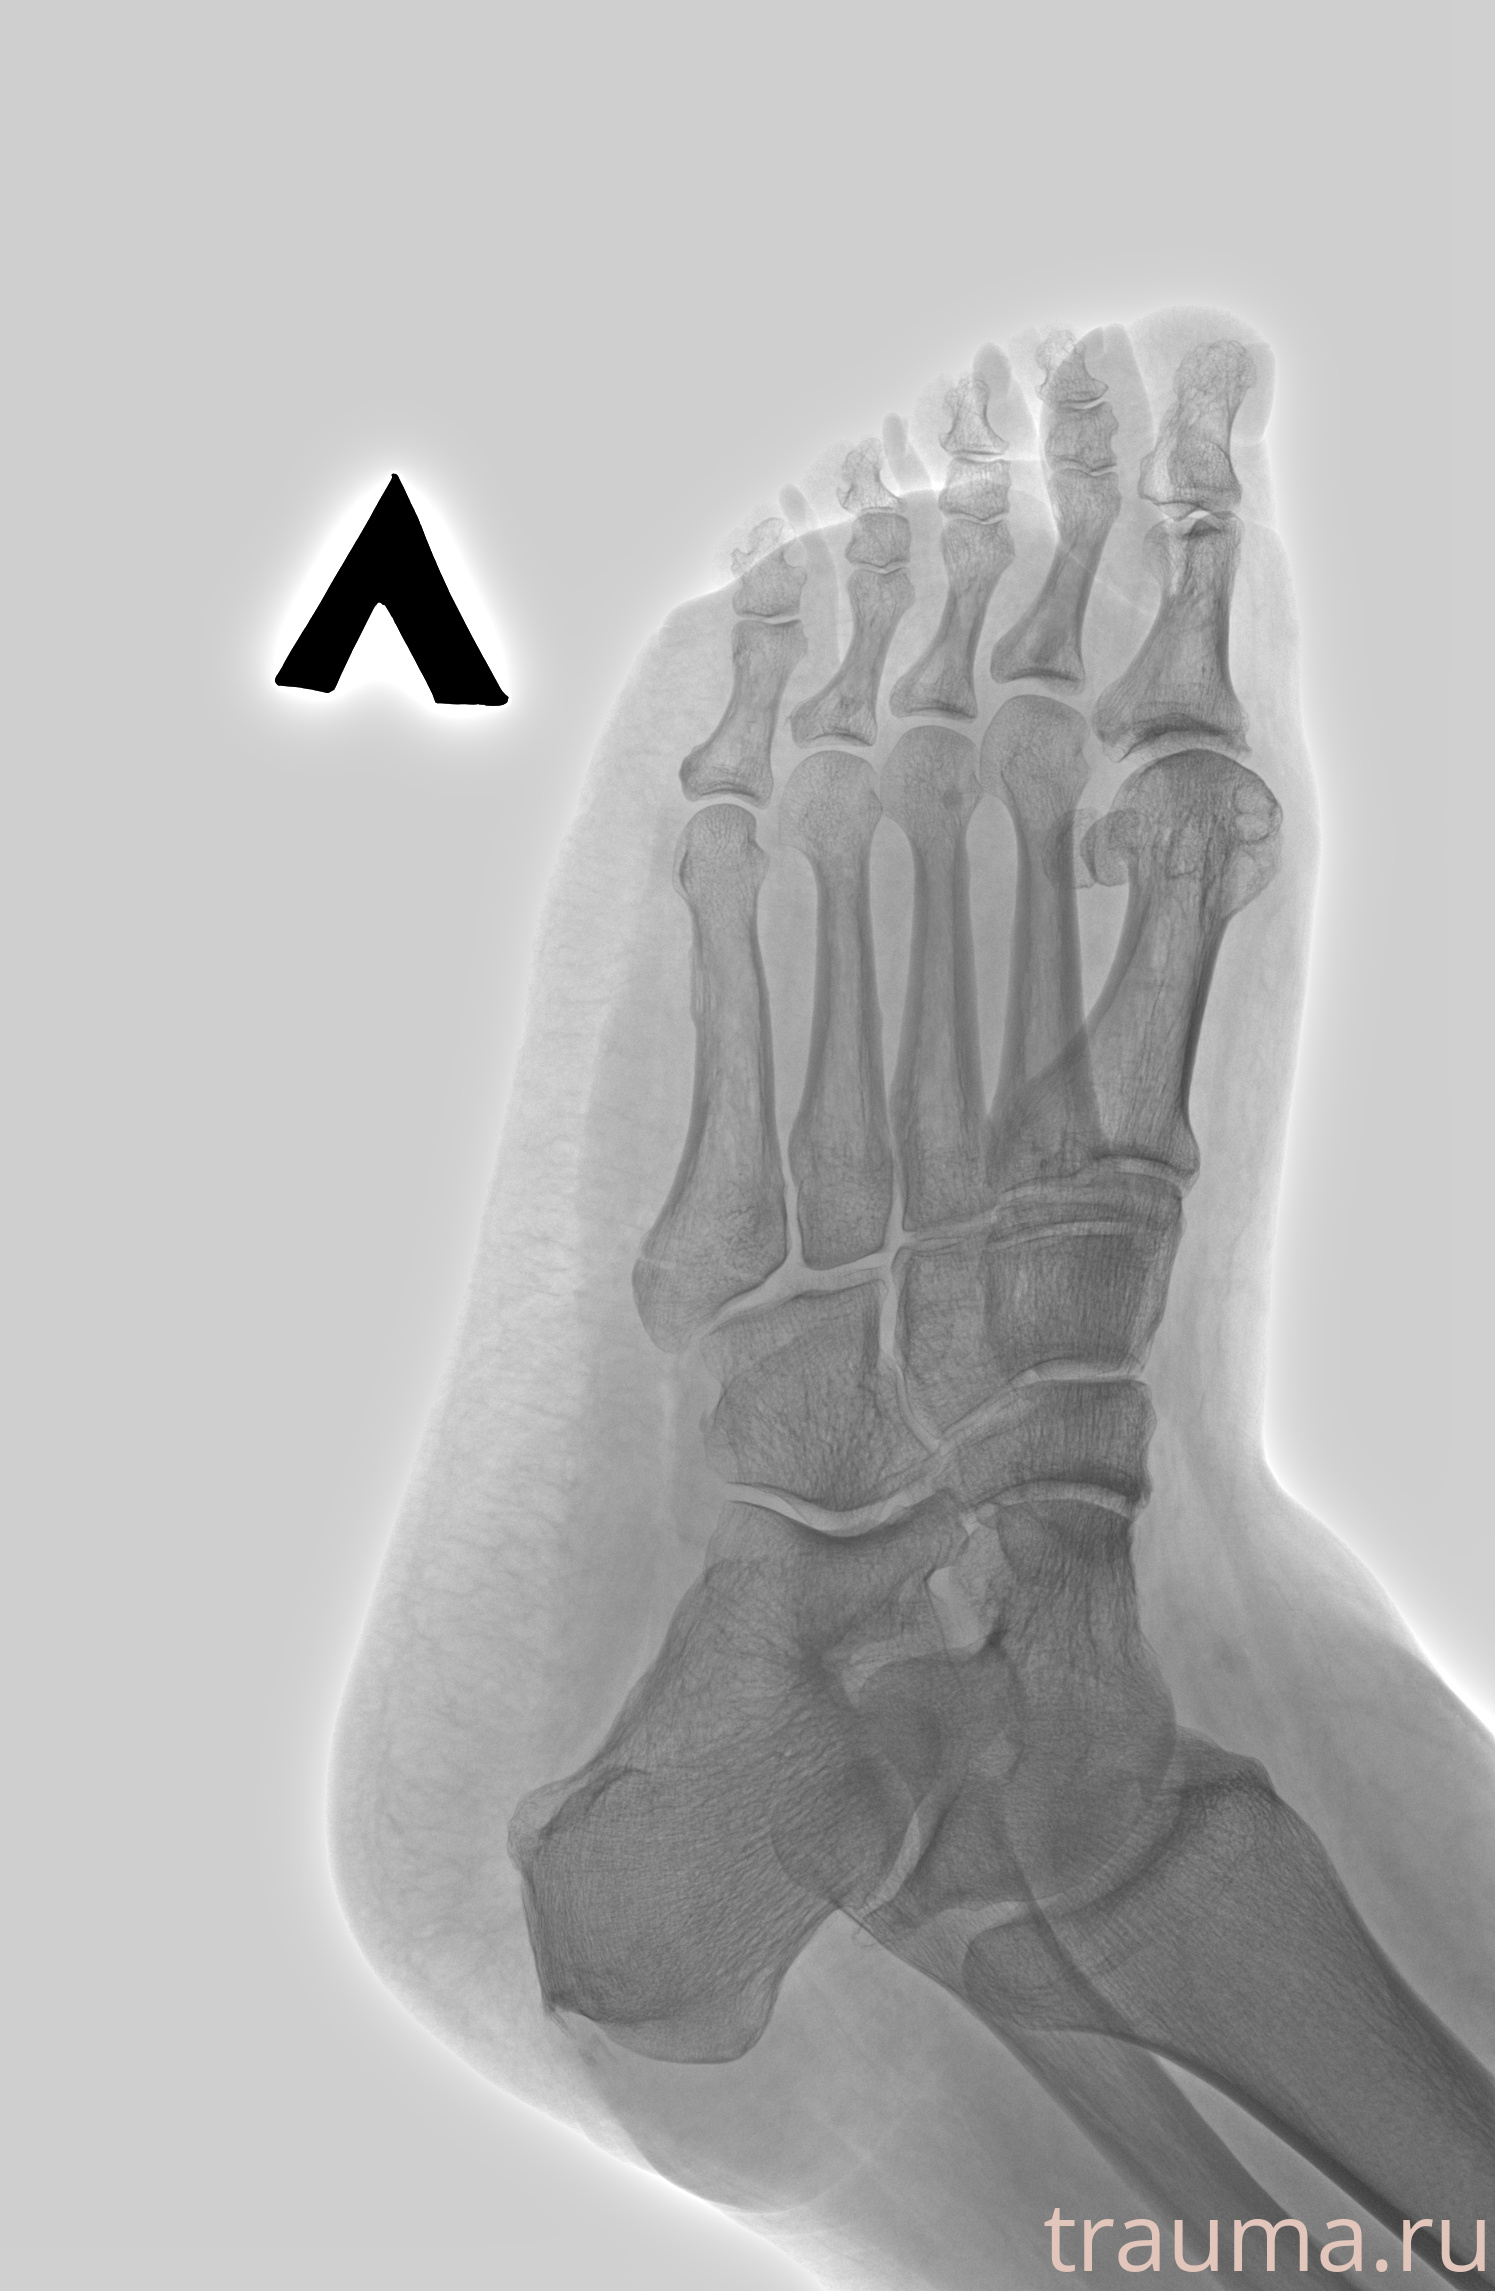

Рентгенограммы

Рентген на дому: по вашему адресу приезжает врач-рентгенолог, травматолог-ортопед с мобильным рентгеновским аппаратом, проводит диагностику травмы или заболевания, делает необходимые рентгенограммы, дает рекомендации по дальнейшему лечению. Получить качественные снимки в домашних условиях возможно благодаря уникальной методике, разработанной МосРентген Центром для института  Склифосовского